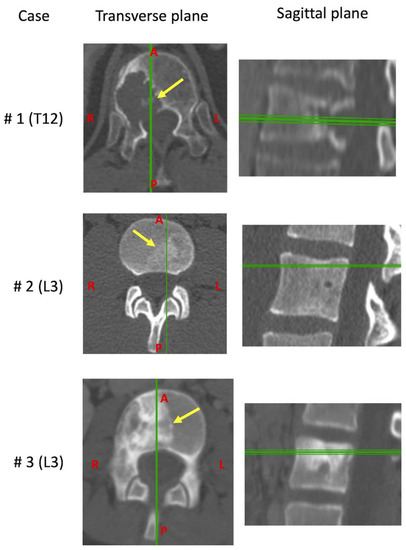

Surgeries were planned and performed according to the location of the lesion in order to minimize the risk of both neurological lesions and marginal contamination. Clinical CT scans were performed the day before the surgery (Figure 2).

Transverse and sagittal planes of the CT scans for each vertebra before the resection. The arrows indicate the position of the tumor, the vertical and horizontal lines indicate the relative position of the plans.

In the first case (#1), the vertebrectomy was performed through a posterior approach and the resection was achieved through the disc above and below. In the second case (#2), a double approach (initially posterior and then combined posterior and anterior extra-pleural retro peritoneal approach) was performed and the resection was achieved through the cranial and caudal adjacent vertebral bodies. In the third case (#3) a double approach similar to specimen #2 was performed and the resection was achieved through the cranial and caudal adjacent discs.